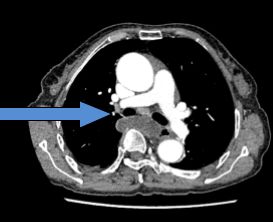

医生立刻急查了凝血功能、心肌酶谱、肌钙蛋白、BNP,又联系了急诊心超和肺动脉CT血管造影术(CTPA)检查,结果报告提示赵老太心肌酶谱、BNP升高,右心室轻度左移,肺动脉收缩压有89毫米汞柱。肺动脉压力这么高,这可急坏了大家。

而CTPA结果提示双侧肺动脉及分支多发栓塞,病情如吕主任所料患者是肺癌合并肺栓塞。此时,赵老太的病情十分危急,属于肺栓塞中高危组,考虑肿瘤病人容易并发出血的风险,暂不予溶栓治疗。事不宜迟,吕主任立即对患者开始抗凝治疗,赵老太的气急情况终于慢慢缓解下来。